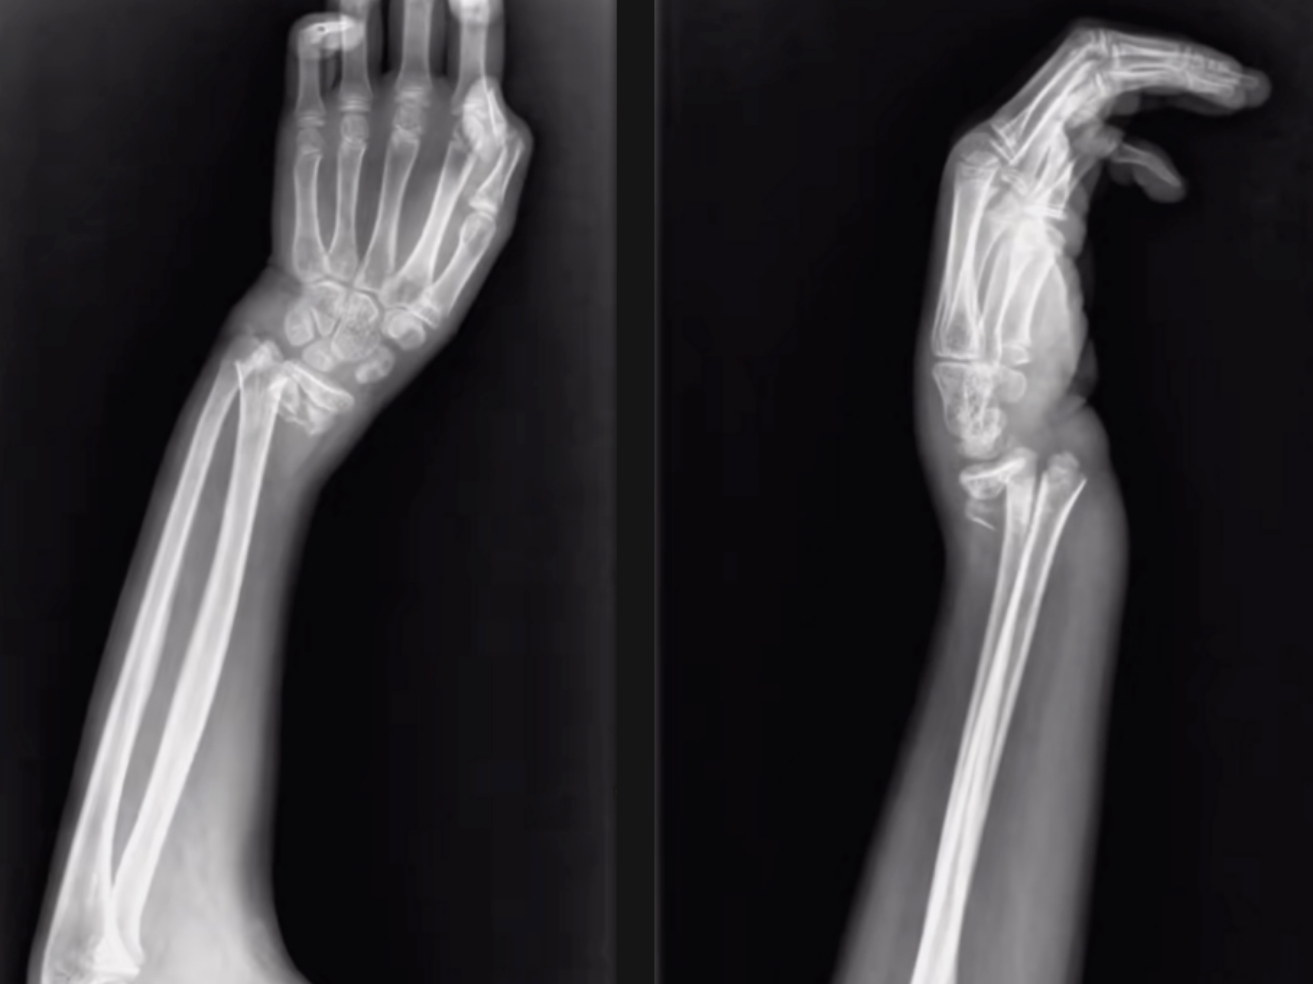

尺橈骨雙骨折復(fù)位前 尺橈骨雙骨折復(fù)位后